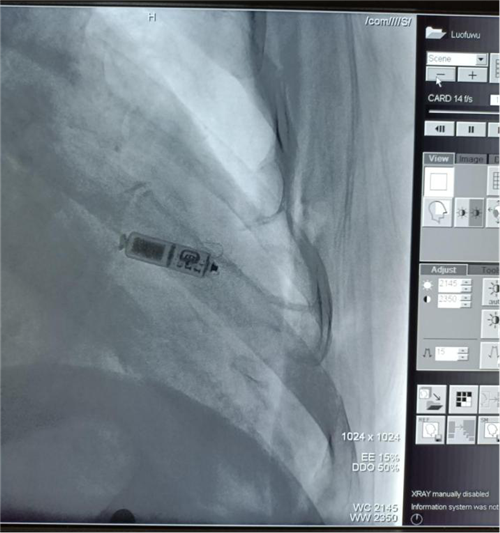

11月21日,东10病区心血管内科团队完成了市内首例无导线心脏起搏器植入手术。

据了解,患者罗某,今年74岁,因“心率减慢8年、头晕及双下肢乏力1天”入院,既往有脑梗死、房颤等病史。入院时,患者心率仅为38次/分,诊断为“Ⅲ度房室传导阻滞”,随时有心跳骤停的可能。心血管内科团队结合患者病情,集体讨论,决定为其实施无线心脏起搏手术。术后患者无不适,复查心电图为起搏心律,手术成功,目前患者已顺利出院。

心血管内科主任医师张昕介绍,无线心脏起搏技术是当今心脏起搏器中前沿的创新技术之一,2013年,奥地利才植入了全球第一例无导线起搏器。这款堪称“世界上最小的起搏器”,体积约1cm3,重量不到2g,仅为一个药物胶囊般大小,它采用将脉冲发生器与起搏电极融缩为一体的方式,直接植入于患者右心室。Micra的适应症与传统单腔起搏器相同,特别针对于有症状的阵发性或永久性房颤合并心动过缓等明确适应症。与传统起搏器相比,无导线起搏可以避免因穿刺操作、及电极和囊袋相关的术后并发症,特别适合于高龄、糖尿病、体瘦患者;无锁骨下静脉通路的起搏适应症患者;感染高危风险、瓣膜病及机械瓣置换患者。在100%起搏时,无导线起搏器使用寿命可达10年左右,且核磁兼容3.0T。有研究表明,与传统有线起搏器相比,无导线起搏器引起的并发症能减少51%!